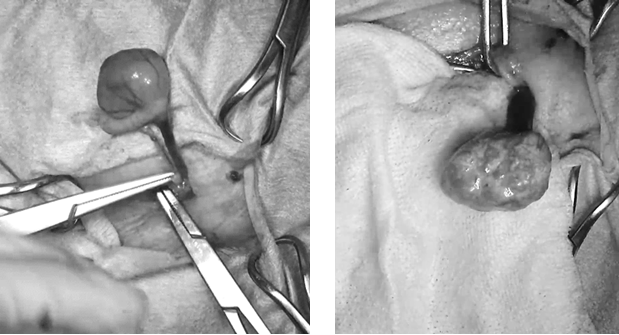

外科手術による肛門周囲腺腫切除および精巣摘出を行いました。下の写真は精巣摘出時に撮影したもので、左が左精巣、右が右精巣です。左精巣は正常に近い形態を保っていましたが、右精巣は大きく腫大し、表面はごつごつとした不整な形をしていました。

切除した肛門周囲の腫瘤と精巣腫瘍の確定診断は、病理検査によって決定します。外部機関に病理検査を依頼したところ、肛門周囲の腫瘤は良性の肛門周囲腺腫および過形成、精巣は左が精上皮腫、右がセルトリ細胞腫と診断されました。